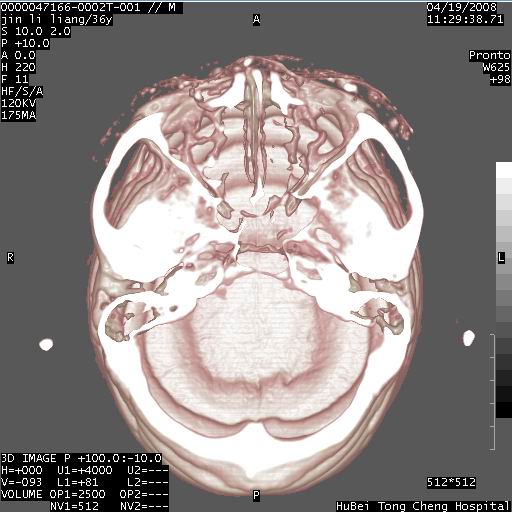

患者 男,36岁。头面部“土炮”炸伤。pe:面目全非,伤口流血不止。

临床诊断:头面部外伤。

颅脑ct轴位平扫(层厚、层距均为10mm),图像如下:

左眼球破裂并异物,眶周、额顶部头皮及软组织挫伤并异物

迎面一炮,满脸开曝。额顶部头皮及软组织挫伤并异物,左眼球破裂积气并异物,典型的面目全非,惨不忍睹。

左眼球破裂积气并异物,眶周、额顶部头皮及软组织挫伤并异物,右侧眼环前内分异物

1左侧眼球破裂并积气,球内、框内异物。

2额部顶部软组织伤。